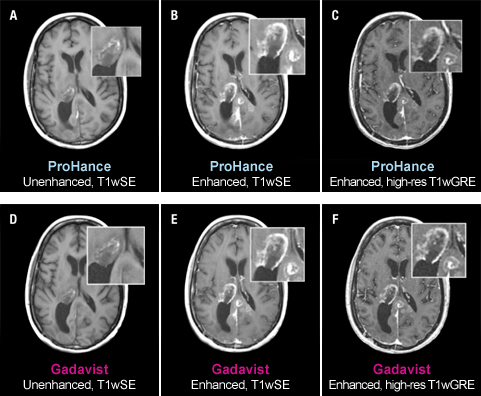

Case Studies

Case Study 2

51-year-old female with glioblastoma multiforme. Rim-enhancing mass in right thalamus with extension into the posterior interhemispheric region is clearly seen in both examinations. No differences in contrast enhancement or in the morphology of lesions are apparent.1

These are representational images from reference studies. Individual results may vary. REFERENCE: 1. Maravilla K, Smith M, Vymazal J, et al. Are there differences between macrocyclic gadolinium contrast agents for brain tumor imaging? Results of a multicenter intraindividual crossover comparison of gadobutrol with gadoteridol (The TRUTH study). AJNR Am J Neuroradiol. 2015;1:14-23, doi: 10.3174/ajnr.A4154.